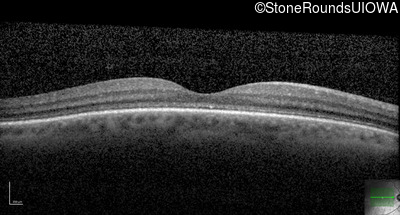

Optical Coherence Tomography - Right - 20/200 sc

Exemplar / OCT Stack

OCT Stack